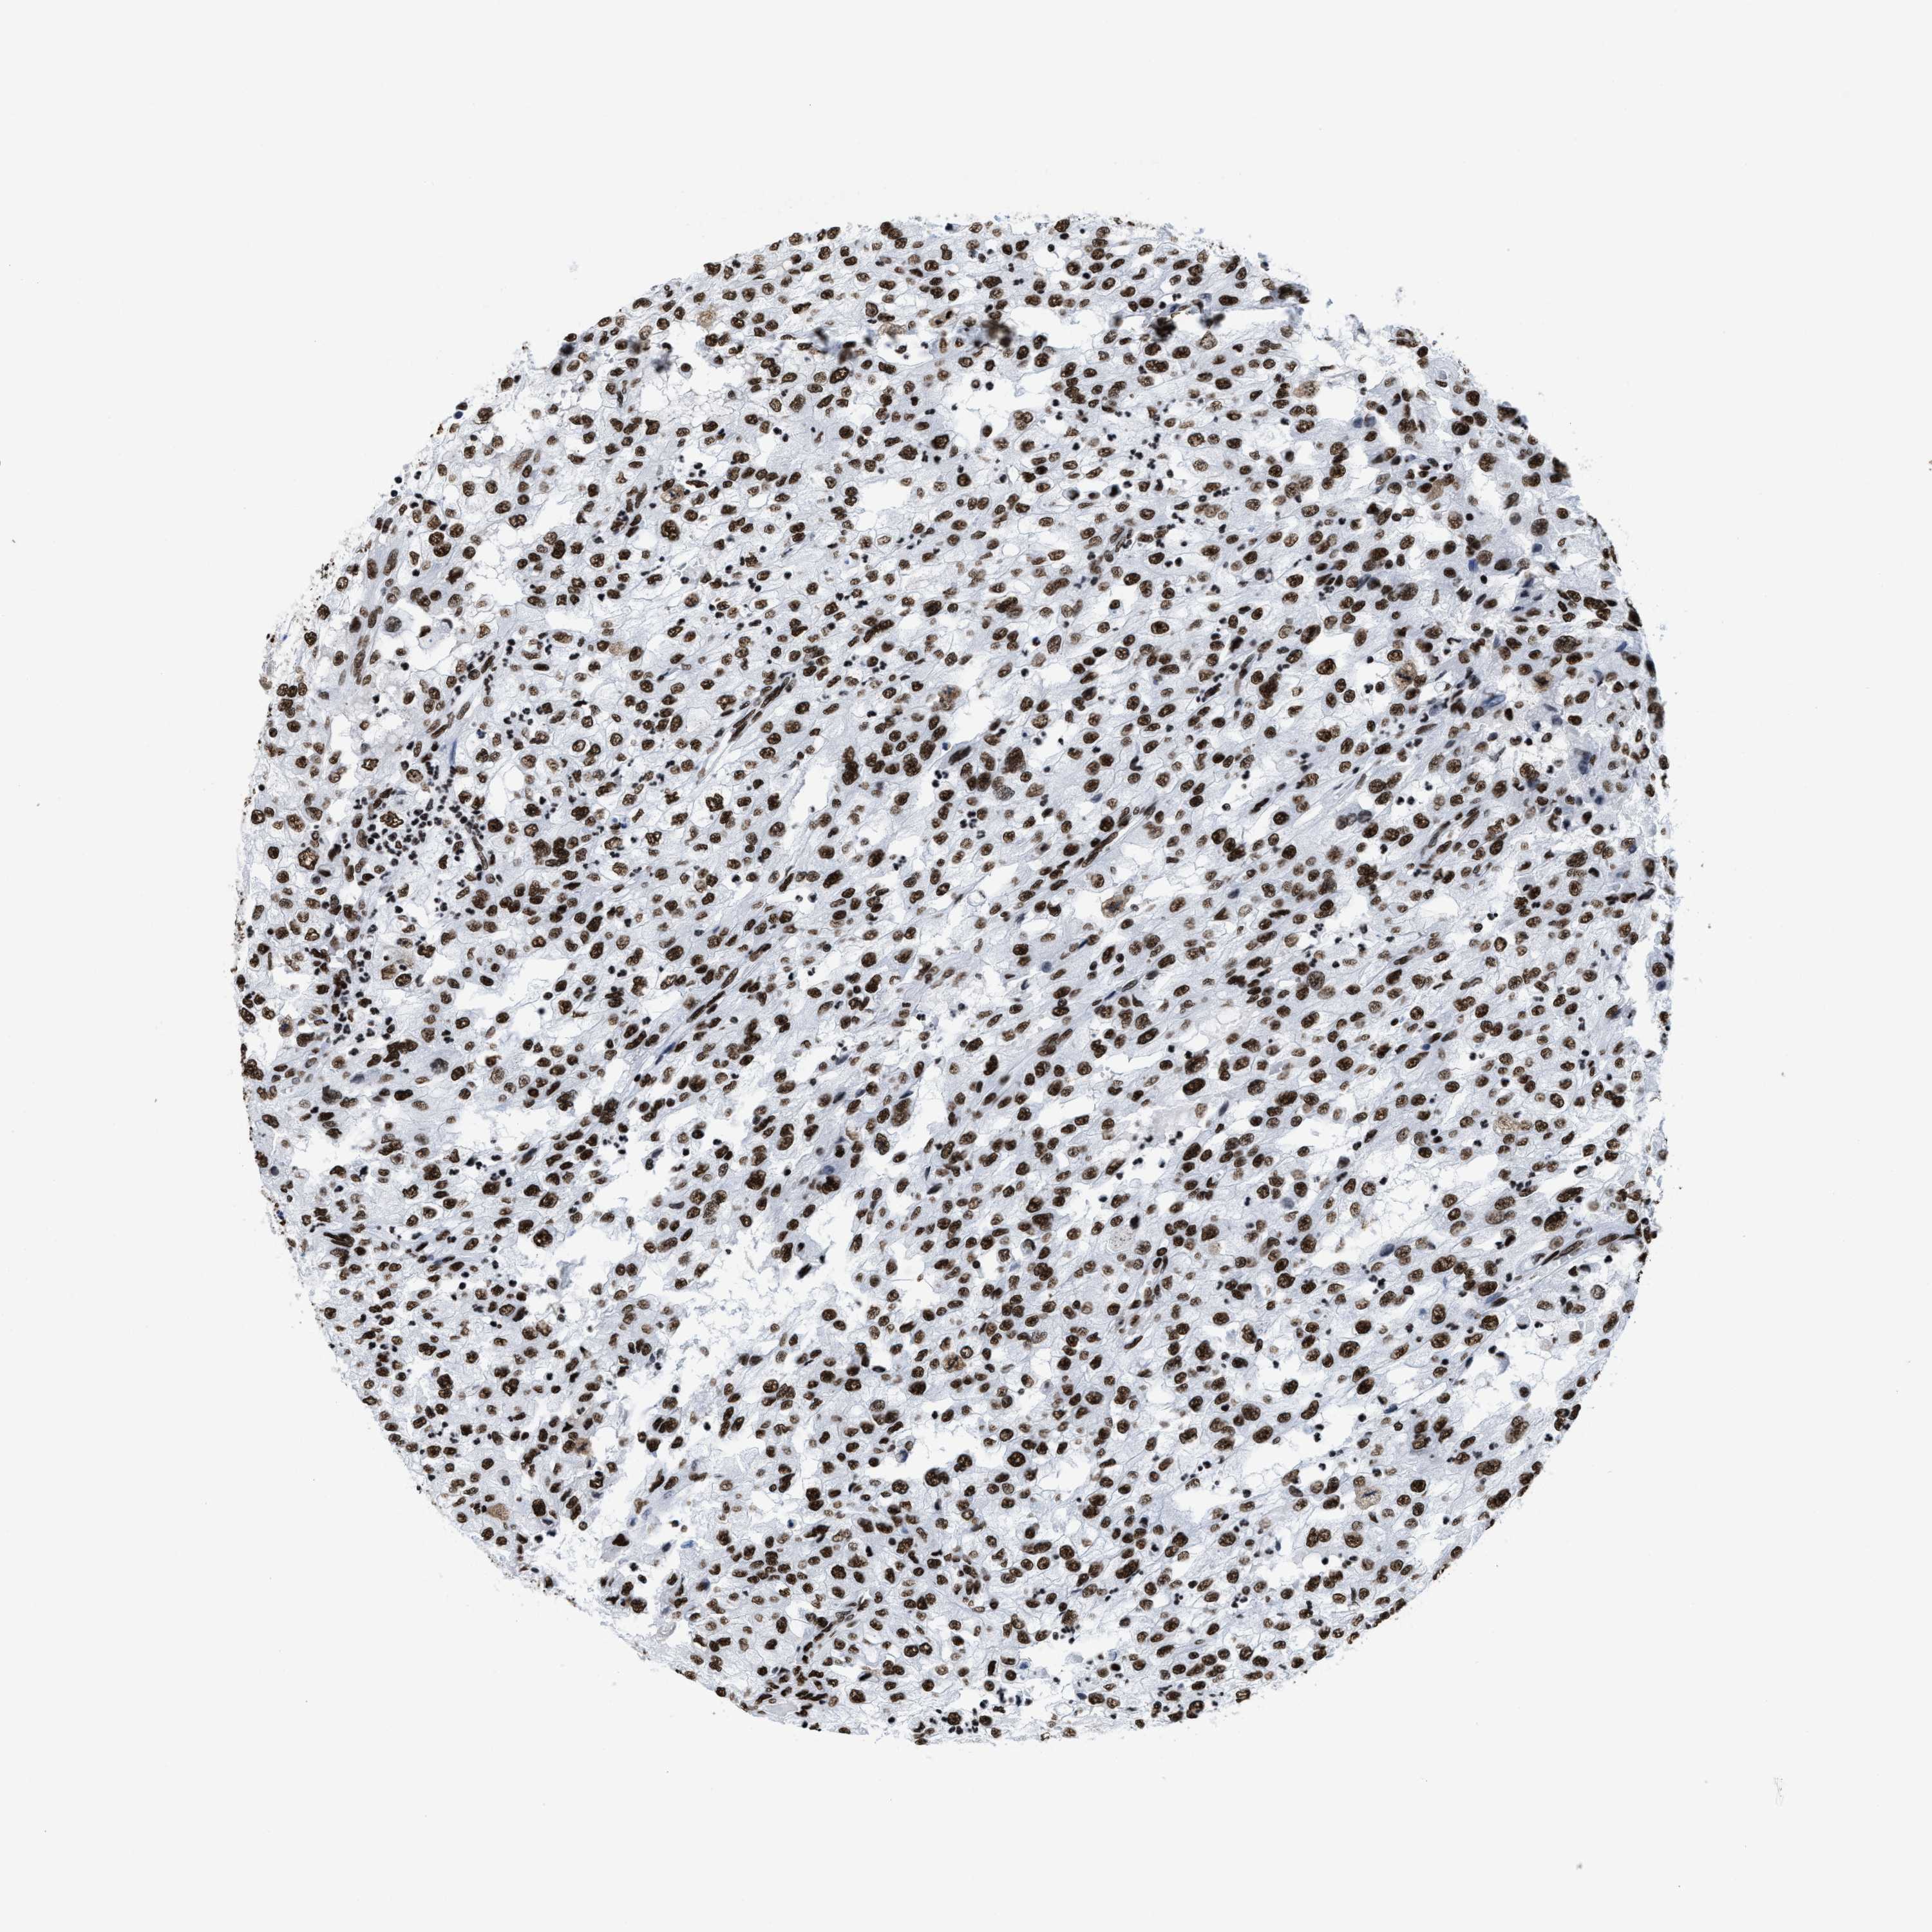

KIDNEY RENAL CLEAR CELL CARCINOMA (VALIDATION) - Interactive survival scatter ploti

The Survival Scatter plot shows the clinical status (i.e. dead or alive) for all individuals in the patient cohort, based on the same data that underlies the corresponding Kaplan-Meier plots. Patients that are alive at last time for follow-up are shown in blue and patients who have died during the study are shown in red.

The x-axis shows the expression levels (FPKM) of the investigated gene in the tumor tissue at the time of diagnosis. The y-axis shows the follow-up time after diagnosis (years). Both axes are complimented with kernel density curves demonstrating the data density over the axes. The top density plot shows the expression levels (FPKM) distribution among dead (red) and alive patients (blue). The right density plot shows the data density of the survived years of dead patients with high and low expression levels respectively, stratified using the cutoff indicated by the vertical dashed line through the Survival Scatter plot. This cutoff is automatically defined based on the FPKM cutoff that minimizes the p-score. The cutoff can be changed by dragging the vertical line or by entering a cutoff value in the square labeled "Current cut-off".

Under the Survival Scatter plot the p-score landscape (black curve; left axis) is shown together with dead median separation (red curve; right axis). Dead median separation is the difference in median mRNA expression between patients who have died with high and low expression, respectively. It is calculated as follows: median FPKM expression of dead patients with high expression - median FPKM expression of dead patients with low expression. This is intended to aid the user in visually exploring custom cutoffs and the associated p-scores and dead median separation.

Individual patient data is displayed and can be filtered by clicking on one or more of the category buttons on the top of the page. Categories describing expression level and patient information include: high, low, alive, dead, female, male and tumor stages. The scale of the x-axis can be toggled between linear and log-scale by clicking on the "x log" button. Mouse-over function shows TCGA ID, patient information and mRNA expression (FPKM) for each patient.

& Survival analysisi

Kaplan-Meier plots summarize results from analysis of correlation between mRNA expression level and patient survival. Patients were divided based on level of expression into one of the two groups "low" (under cut off) or "high" (over cut off). X-axis shows time for survival (years) and y-axis shows the probability of survival, where 1.0 corresponds to 100 percent.

SMARCC2 is not prognostic in Kidney Renal Clear Cell Carcinoma (validation)

Best expression cut offi

Based on the FPKM value of each gene, patients were classified into two groups and association between prognosis (survival) and gene expression (FPKM) was examined. The best expression cut-off refers the FPKM value that yields maximal difference with regard to survival between the two groups at the lowest log-rank P-value. Best expression cut-off was selected based on survival analysis .

When clicking on this number, the vertical dashed line indicating cut-off, the interactive survival plot, and the Kaplan-Meier curve will be adjusted to show results based on the best expression cut-off.

: 44.04

Median expressioni

Median expression refers to the median FPKM value calculated based on the gene expression (FPKM) data from all patients in this dataset. When clicking on this number, the vertical dashed line indicating cut-off, the interactive survival plot, and the Kaplan-Meier curve will be adjusted to show results based on the median expression.

: N/A

Median follow up timei

Median follow up time refers to the median time (years) after diagnosis with this type of cancer, based on clinical data from all patients in this dataset.

P scorei

Log-rank P value for Kaplan-Meier plot showing results from analysis of correlation between mRNA expression level and patient survival.

N/A

5-year survival highi

5-year survival for patients with higher expression than the expression cutoff.

For melanoma and glioma, 3-year survival is shown.

5-year survival lowi

5-year survival for patients with lower expression than the expression cutoff.

TCGA RNA samplesi

RNA-seq data is reported as average FPKM (number Fragments Per Kilobase of exon per Million reads), generated by the The Cancer Genome Atlas (TCGA) .

Normal distribution across the dataset is visualized with box plots, shown as median and 25th and 75th percentiles. Points are displayed as outliers if they are above or below 1.5 times the interquartile range. FPKM values of the individual samples are presented next to the box plot.

Average pTPM 43.8

Number of samples 100